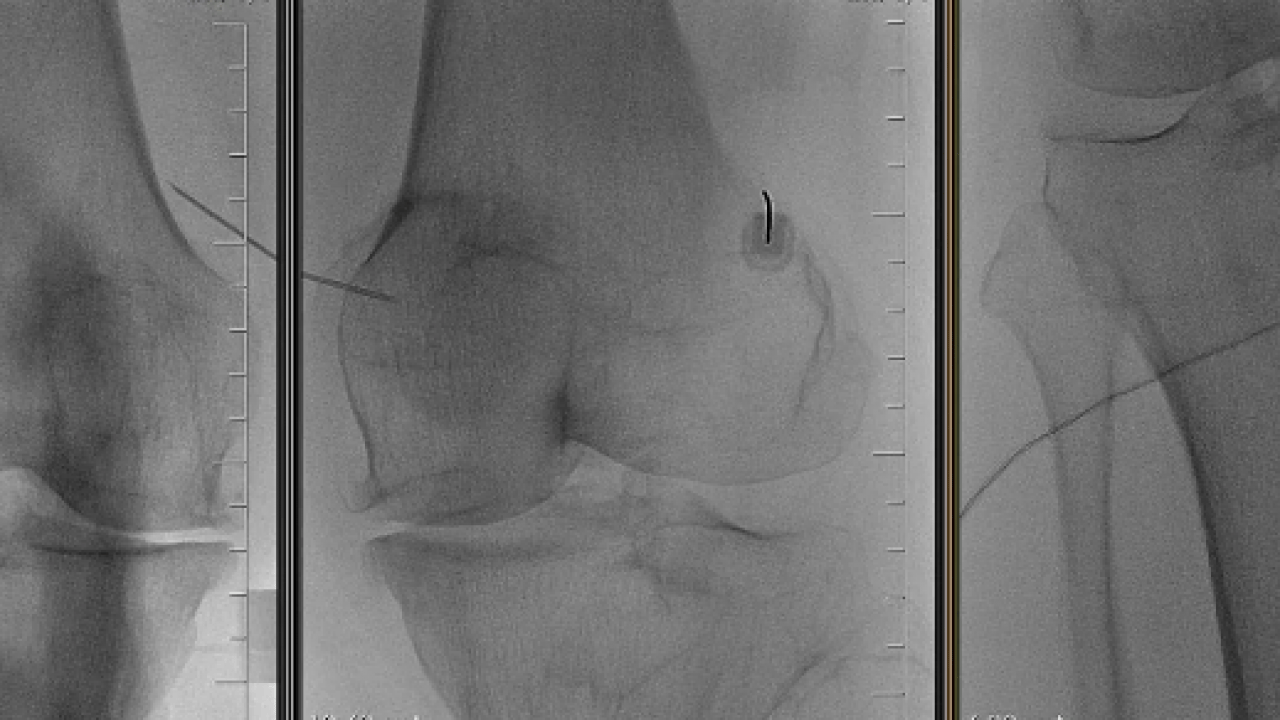

Radyofrekans tedavisinin, ağrıya neden olan sinirlerin kontrollü şekilde tedavi edilmesi esasına dayandığını belirten Prof. Dr. İrfan Koca, "Bu yöntemde özel iğneler aracılığıyla hedef sinir dokusuna ulaşılır ve radyo dalgaları kullanılarak ağrı iletimi azaltılır. Minimal invaziv bir işlem olup genellikle kısa sürede tamamlanır" dedi.

Tedavinin özellikle uygun hasta grubunda etkili sonuçlar verdiğini vurgulayan Koca, "Radyofrekans tedavisi; fizik tedavi, manuel terapi, kuru iğneleme, nöral terapi, proloterapi gibi konservatif ve girişimsel tedavi yöntemlerine rağmen yeterli yanıt alınamayan ve ağrıları devam eden hastalar açısından önemli bir tedavi seçeneğidir. Bununla birlikte, şikayetlerinin kaynağı cerrahi gerektiren bir patolojiye dayanmayan ya da kendisine cerrahi tedavi önerilmiş olmasına rağmen ameliyatı tercih etmeyen hastalar için de etkili ve güvenilir bir alternatif tedavi seçeneği olarak karşımıza çıkmaktadır" ifadelerini kullandı.

Uygun hasta seçiminin tedavi başarısındaki en önemli faktörlerden biri olduğuna dikkat çeken Koca, "Her ağrıya uygulanabilecek bir yöntem değildir. Doğru endikasyonla uygulandığında hastaların yaşam kalitesinde belirgin iyileşme sağlanabilir" şeklinde konuştu.

İşlem sonrası sürecin konforlu olduğunu belirten Koca, "Radyofrekans tedavisinin en önemli avantajlarından biri ameliyatsız bir yöntem olmasıdır. İşlem sonrasında hastalar genellikle saatler içinde günlük yaşamlarına dönebilmektedir" dedi.

Yan etkilerin genellikle sınırlı olduğunu ve işlemin deneyimli hekimler tarafından yapılması gerektiğini belirten Koca, "Uygun teknik ve doğru hasta seçimi ile komplikasyon riski oldukça düşüktür" şeklinde konuştu. Uzmanlar, kronik ağrı tedavisinde radyofrekans yönteminin özellikle diğer tedavilere yanıt vermeyen ve cerrahi dışı çözüm arayan hastalar için etkili ve güvenilir bir seçenek sunduğunu belirtiyor.